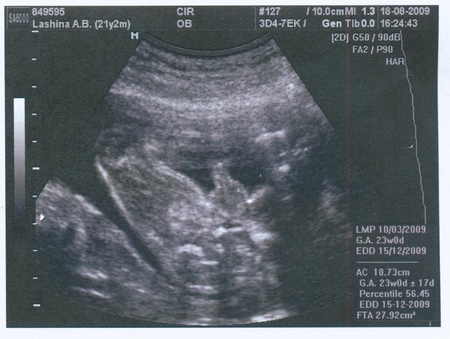

Тут на 18-19 неделек - растём!